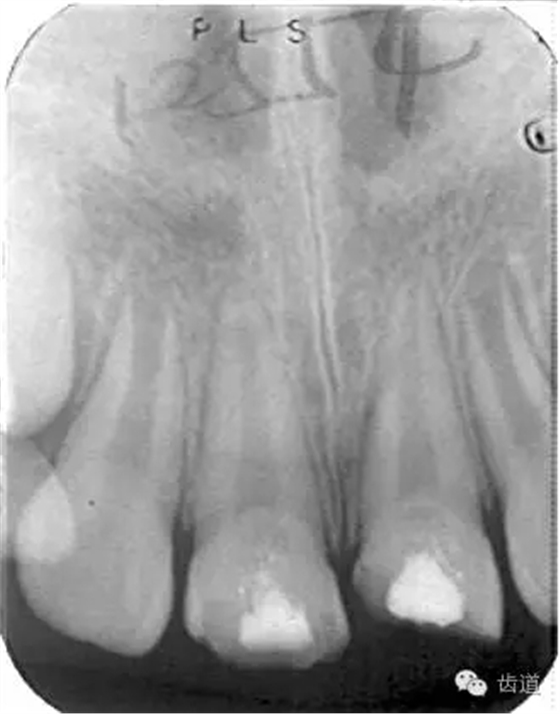

術(shù)后

術(shù)前

術(shù)后199日

術(shù)后1084日